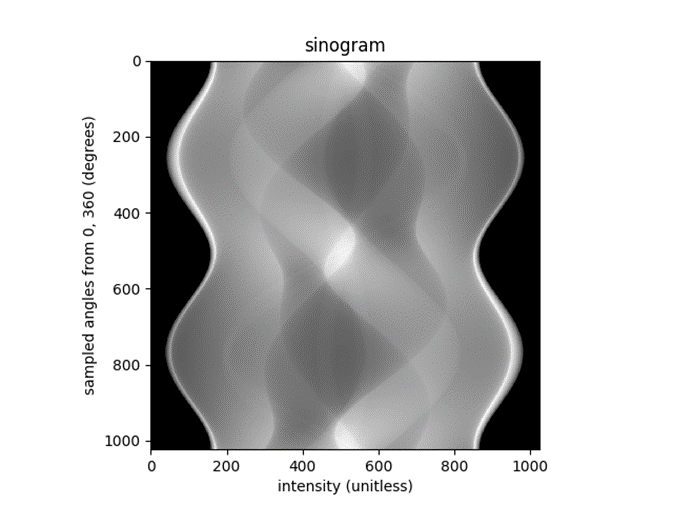

As previously discussed with in the Background, to reconstruct and image firstly the image must be back projected to create a sinogram. Although this method will lose value due to polar sampling within the Fourier slice theorem. Using the reference image that was outlined within the Introduction, the sinogram of this image can be seen in Figure 4. The reconstruction from this sinogram can be seen in Figure 5.

Figure 4: sinogram of shepp-logan phantom

Figure 4: sinogram of shepp-logan phantom